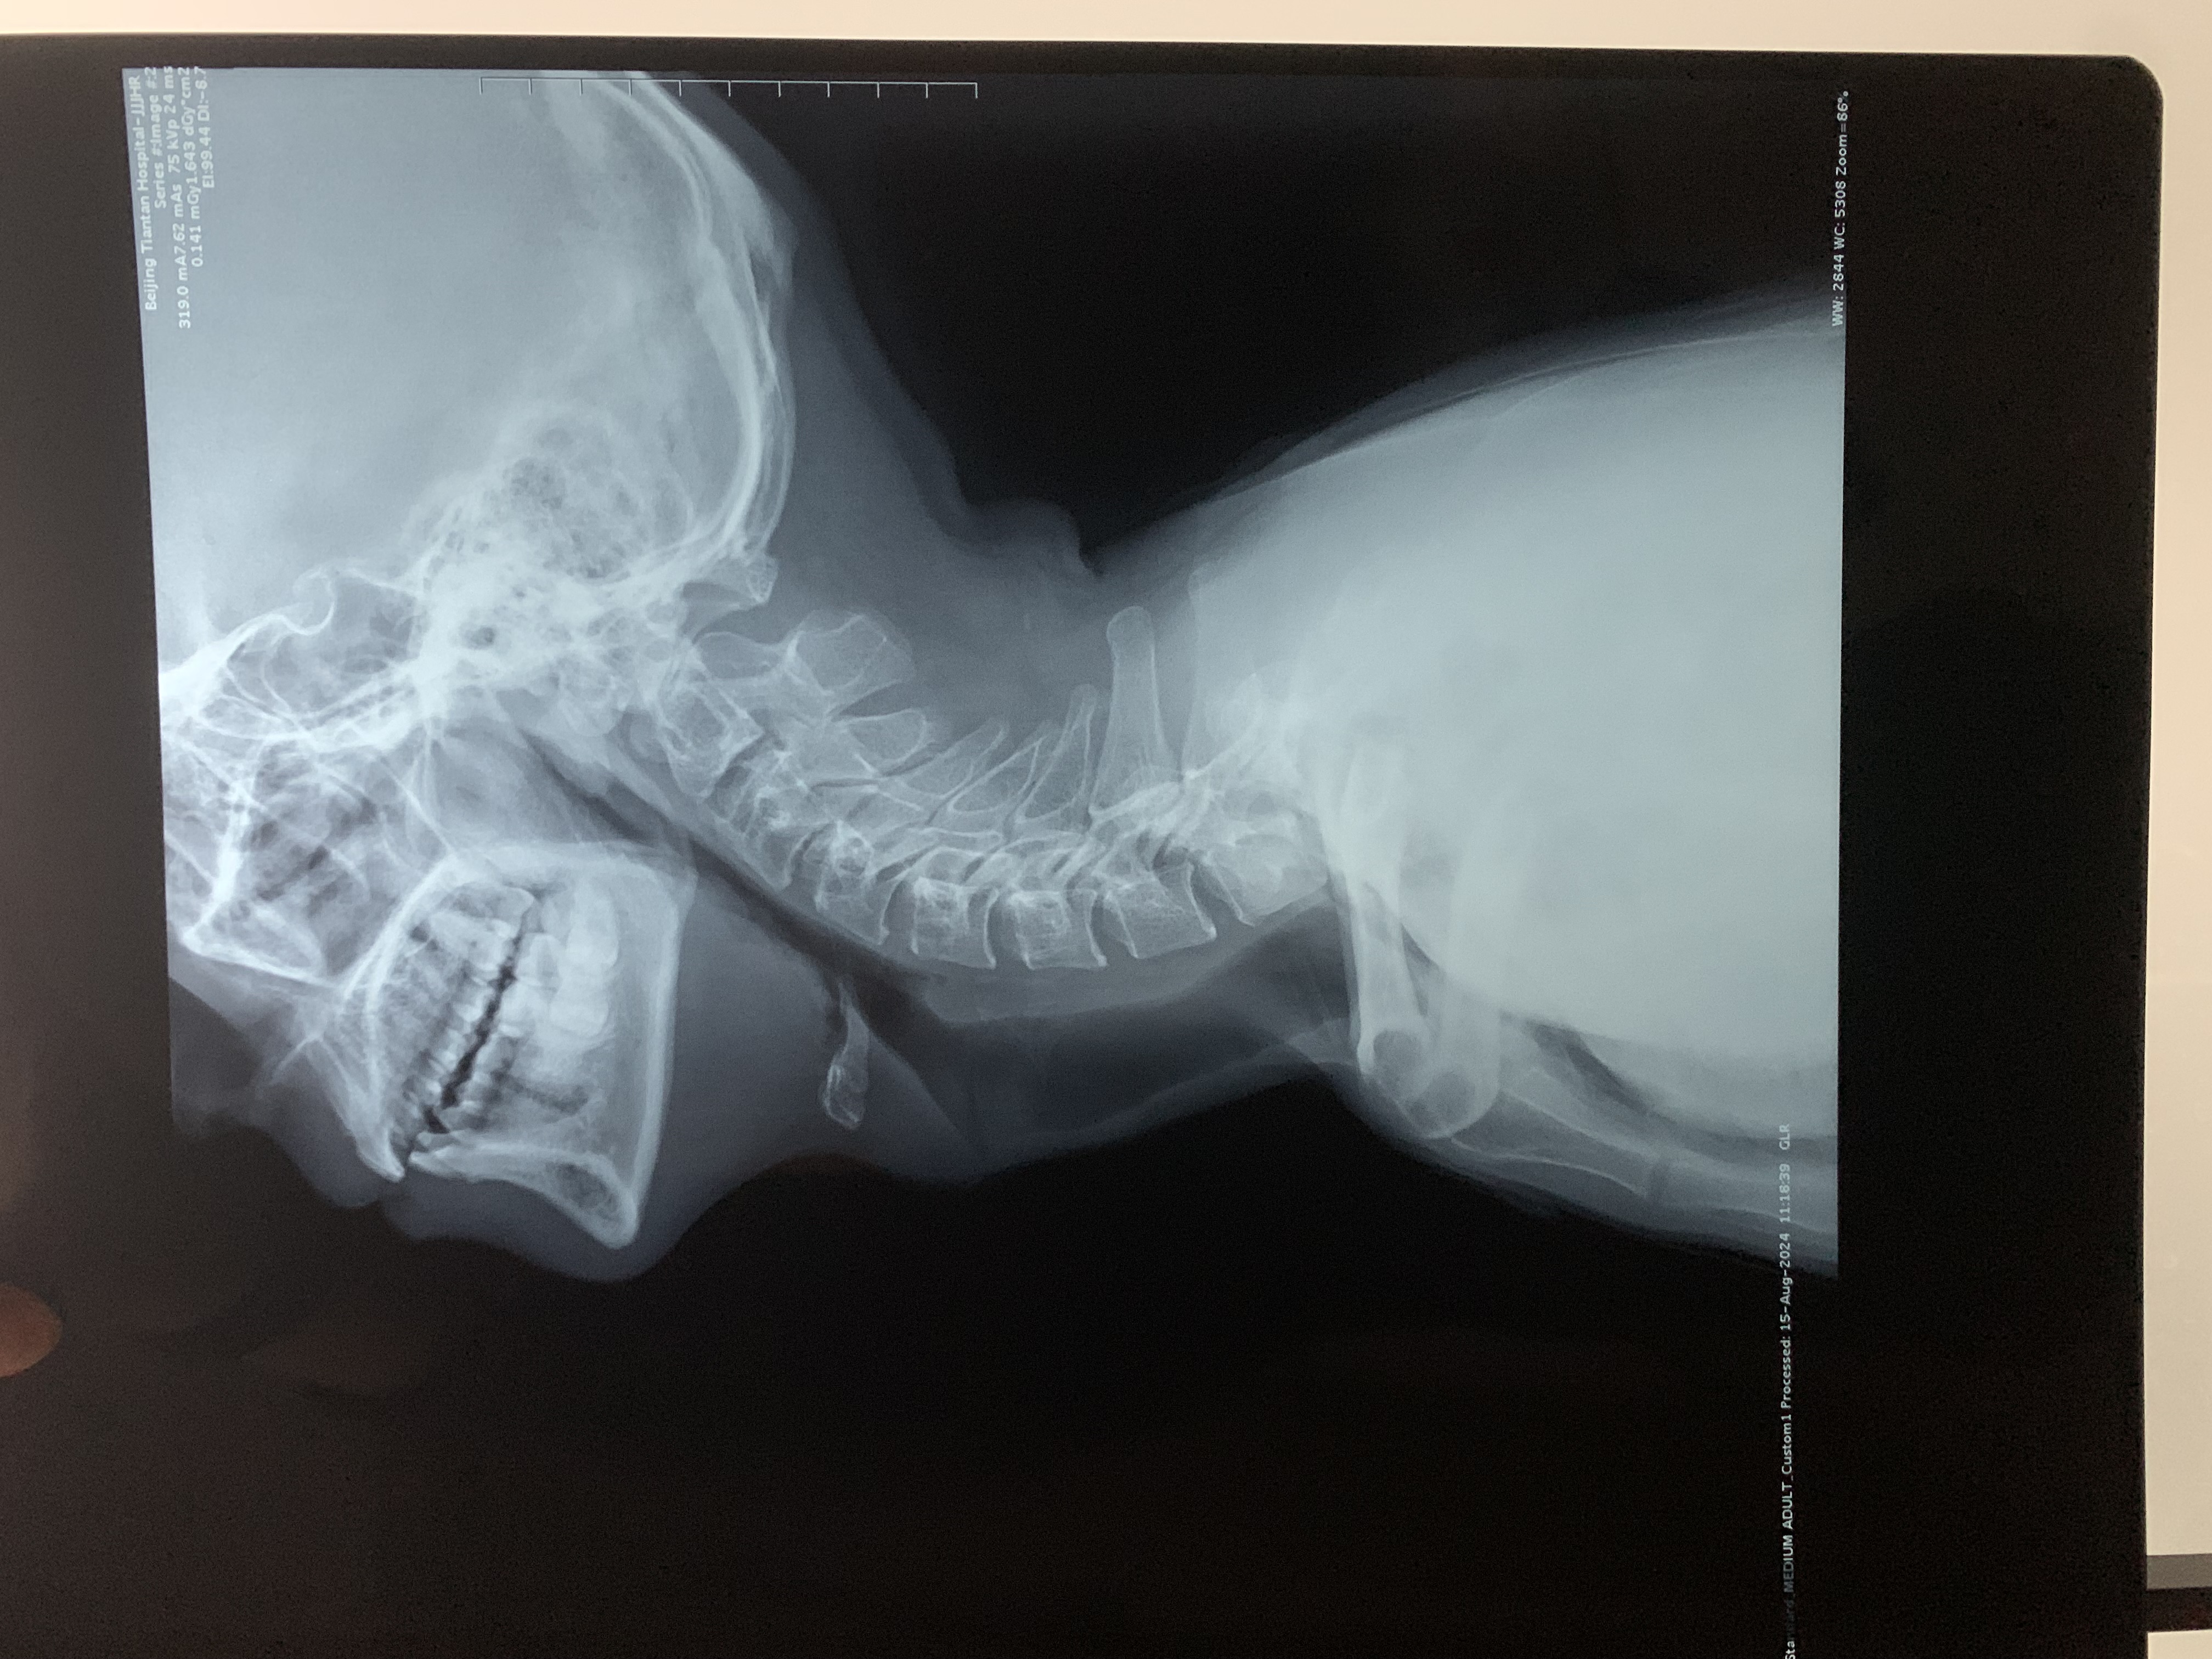

• 诊断:寰枢椎脱位、颅底凹陷

• 影像: